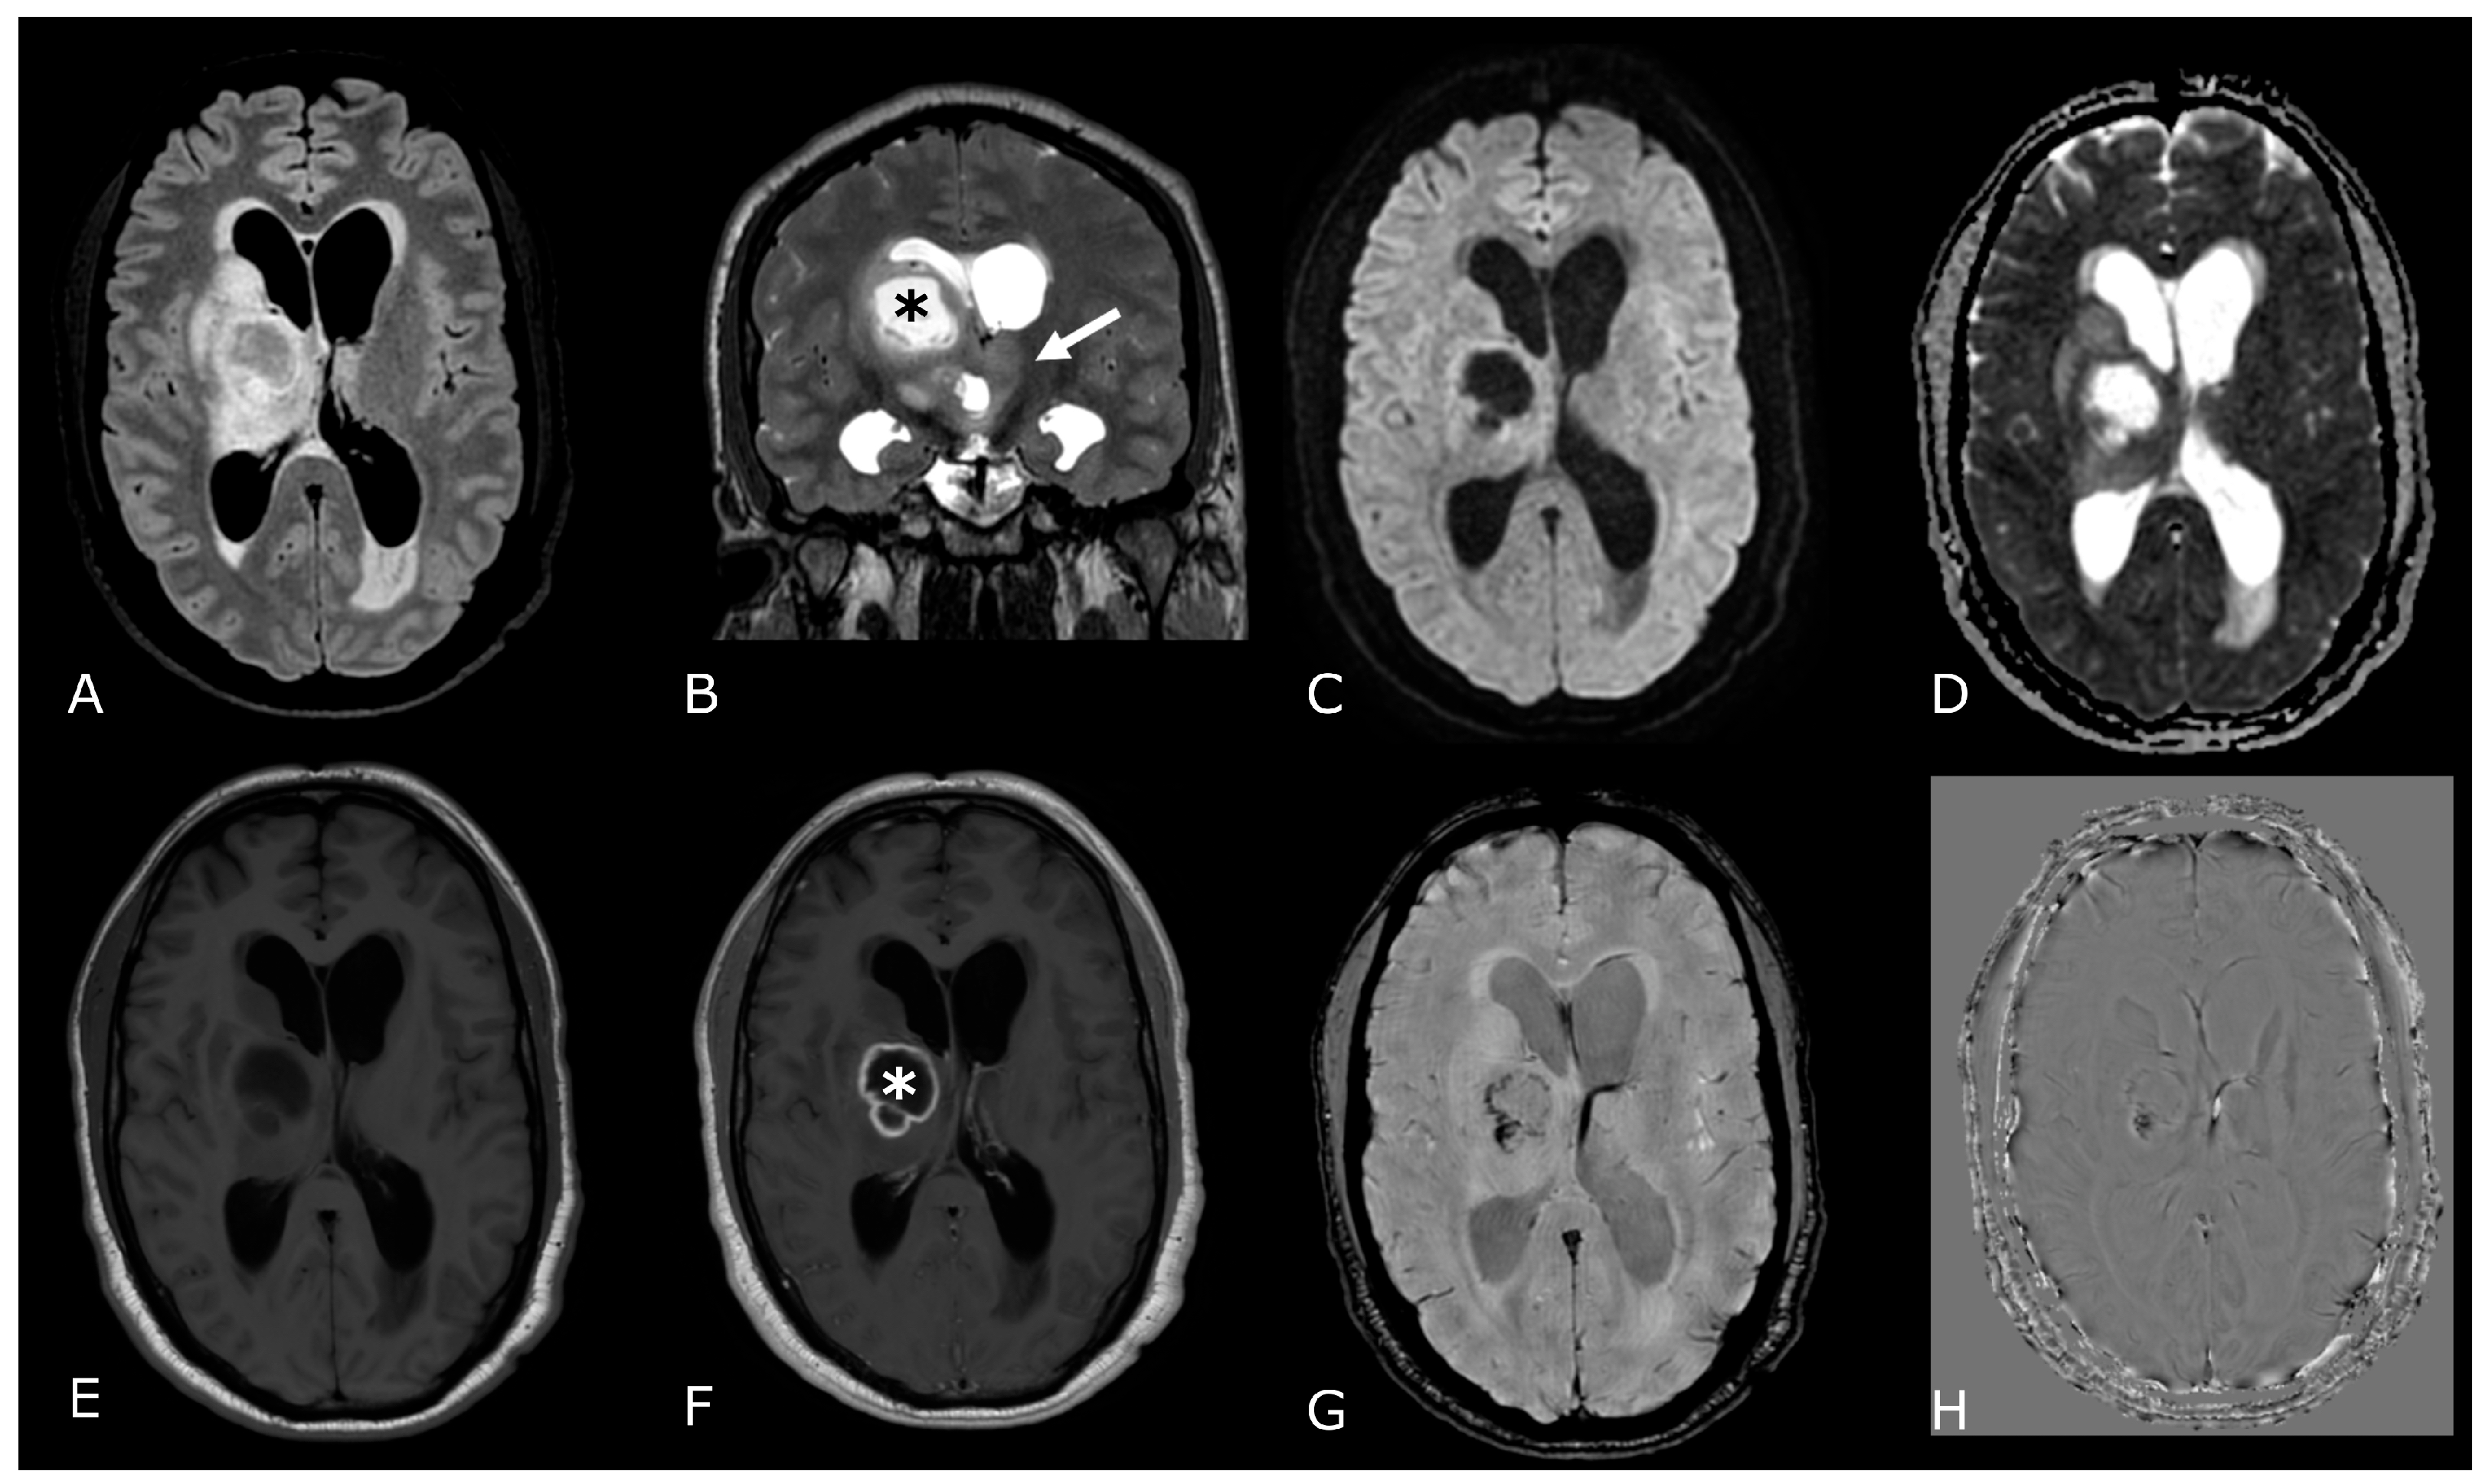

Figure 2.

Conventional MR sequences: necrosis and hemorrhages. Right deep thalamo-capsular IDH-wt GB. The lesion shows a necrotic core (asterisk in (B,F)) and a thick and irregular rim of hypercellular tissue with restricted diffusion (C,D) and contrast-enhancement ((F) compared to (E)). (G,H) demonstrate hemosiderin marginal deposits (hypointense on both SWI and phase-map respectively) suggestive of intratumoral bleedings. The “rim enhancing” lesion is surrounded by a peripheral heterogeneous area of abnormal T2w/FLAIR signal (A,B), reflecting infiltrative “non enhancing” tumor and vasogenic edema that also involves the mesial surface of the contralateral thalamus and hypothalamus (arrow in (B). The caudal extension determines stenosis of the Sylvian aqueduct and consequently supratentorial hydrocephalus.

SWI can help differentiate calcification from hemorrhages because calcification is diamagnetic, whereas most hemorrhagic byproducts are paramagnetic. Due to their opposite magnetic susceptibilities, their phase deflections are opposite as well [9]. Dense coarse calcifications are seen in 34–80% of oligodendrogliomas (ODs) [10], making them the intra-axial tumors with the highest frequency of calcification among BTs. Although the likelihood of an OD is high for a calcified supratentorial intraparenchymal tumor, the differential diagnosis of a calcified intra-axial intracranial mass includes other tumors, such as ependymomas and low-grade astrocytomas.

Cystic components are more frequently associated with lower grade gliomas (e.g., pilocytic astrocytoma). On the contrary, intra-tumoral necrotic areas are mostly seen in higher grade tumors and depicted as areas of lack of enhancement on post gadolinium-based contrast agent (GBCA) T1w images (Figure 2F) [11].

Ultimately, intratumoral contrast enhancement is generally considered to be associated with higher tumor grade, although certain low-grade gliomas (LGG), such as pilocytic astrocytomas, generally enhance and certain high-grade gliomas (HGG) may not (Figure 1F) [12].

Finally, the presence of any of the following five histologic and molecular criteria is sufficient to designate an IDH-wt diffuse astrocytic glioma as a GB (grade 4 by definition): microvascular proliferation, necrosis, telomerase reverse transcriptase promoter (TERTp) mutation, epidermal growth factor receptor (EGFR) gene amplification, and +7/−10 chromosome copy number changes. At MRI, GBs typically present more aggressive and heterogenous morphological features: larger lesions, relevant mass effect and surrounding edema, intratumoral hemorrhage and necrosis, thick ring or irregular/multinodular contrast enhancement (Figure 2).